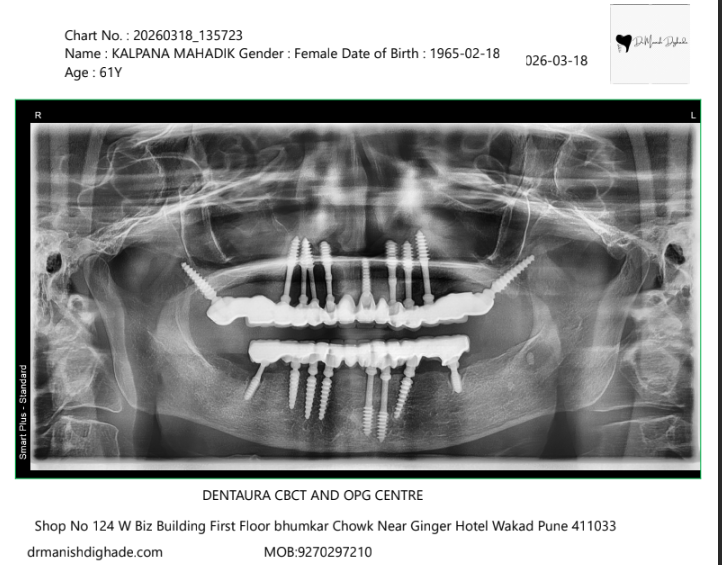

X-Ray Analysis

OPG — Before

Radiographic Findings

The X-ray shows multiple dental implants placed in both upper and lower jaws. These implants are positioned strategically to provide strong support for full arch fixed teeth. This allows immediate loading and ensures stability, function, and long-term success of the treatment.